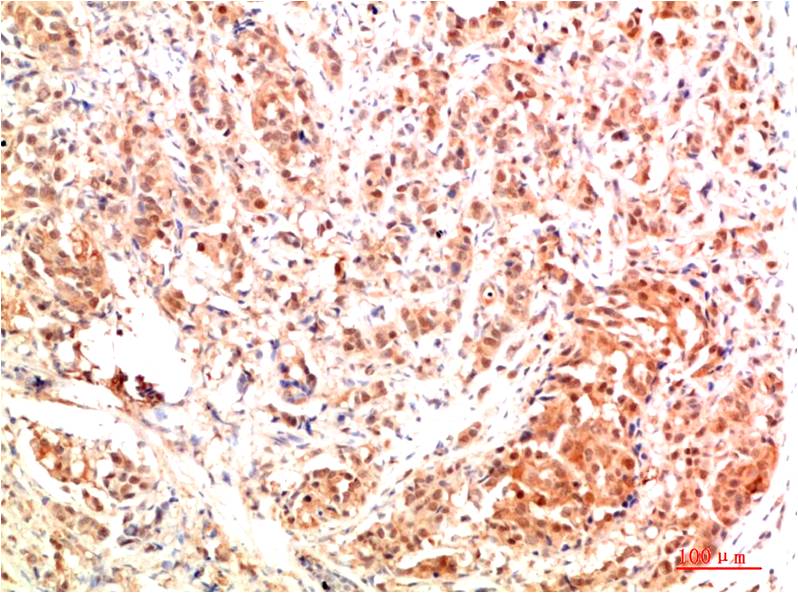

STAT1 Rabbit Polyclonal Antibody

Catalog NO.:BE3403

Applications :WB, IHC

Reactivity :H,R,M

STAT1 is a member of the Signal Transducers and Activators of Transcription family of transcription factors. STAT1 is involved in upregulating genes due to a signal by either type I, type II, or type III interferons

| Recommended dilutions: | WB:1:1,000-2,000 IHC:1:200-500 |

| Specificity: | Antibody can detects endogenous STAT1 protein. |